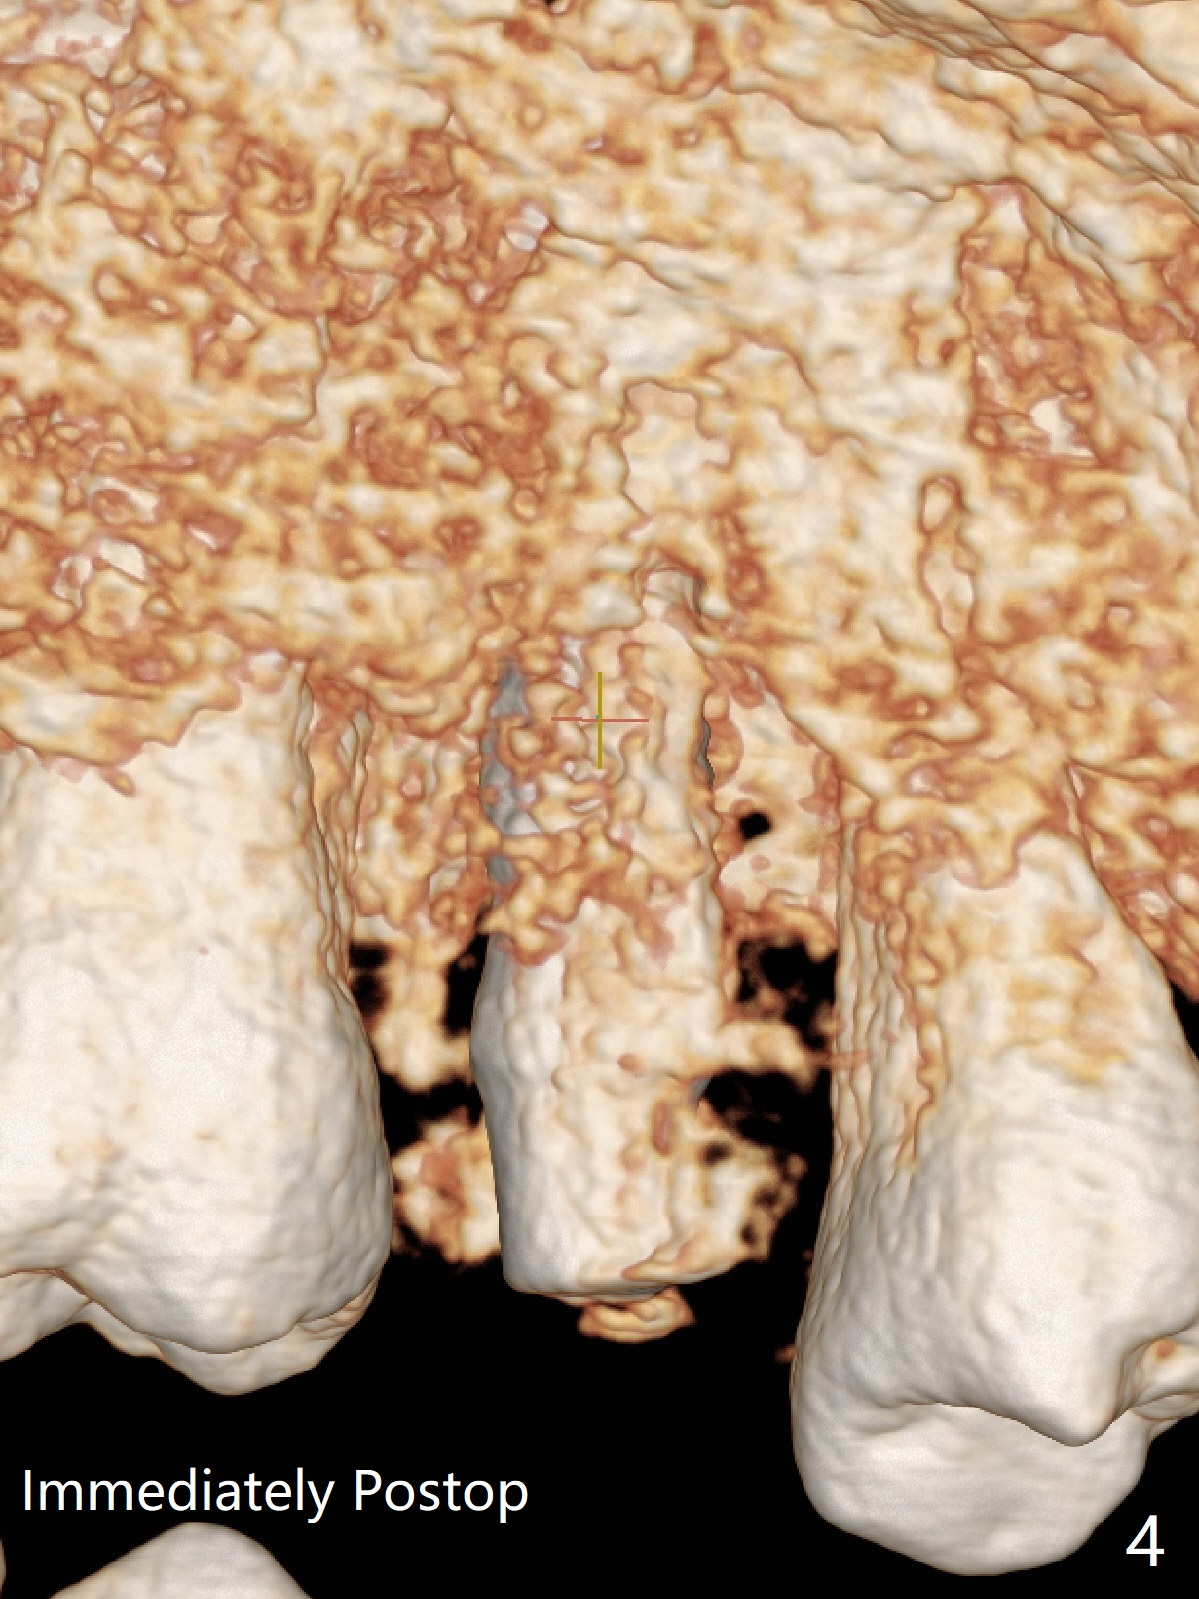

DIO lab refuses fabricating guide because of the large socket and recommends extraction and socket preservation at #13. Due to short apical bone (Fig.5,7), a long dummy implant (3.8x15 mm) is placed with periimplant space immediately post extraction (Fig.1 *). The final implant is larger (4.5x15 mm) with simultaneous sinus lift and periimplant bone graft (Fig.2,6,8 *). To repair the palatal crest defect (Fig.3 *) associated with tooth fracture (Fig.5 white dashed line), the implant is not placed too palatal with sufficient amount of the bone graft (Fig.4,6 *). The native bone (higher in bone density, Fig.9 white arrowheads, as compared to black one (for bone graft)) appears to have grown into the space between implant threads 5.5 months postop. The permanent crown/abutment is loose 1 year 9 months post cementation; after proximal reduction (Fig.10 arrowheads), the abutment is reseated completely. Pick up impression is taken and a healing abutment is placed. A few days later, the crown and abutment (separate) are seated passively; the abutment screw is retightened; the crown is re-cemented. The crown and abutment is removed for residual cement removal (Fig.11). Since there is mild buccal plate atrophy (Fig.11 B), the crown has a buccal lip (Fig.12 B) to prevent food impaction. The lip makes it difficult to remove residual cement intraorally. Therefore an access hole is necessary (Fig.13).